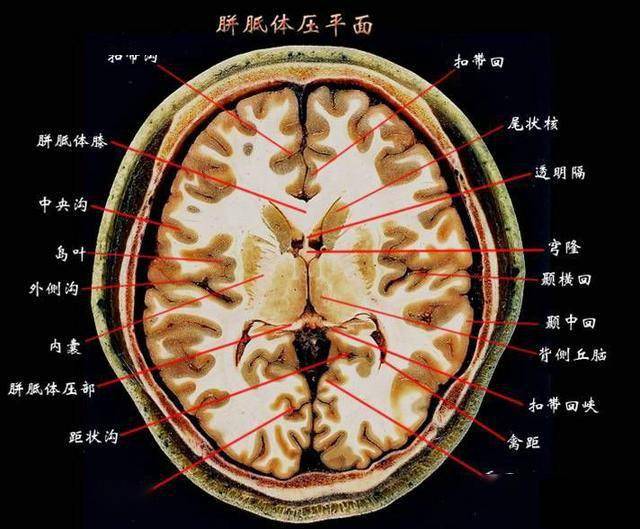

第三脑室 向 室 前 间 上 孔 经 通 左 侧 脑 室 向后下经中脑水管通

brain:大脑③ lateral ventricle:侧脑室④ third ventricle:三脑室⑤